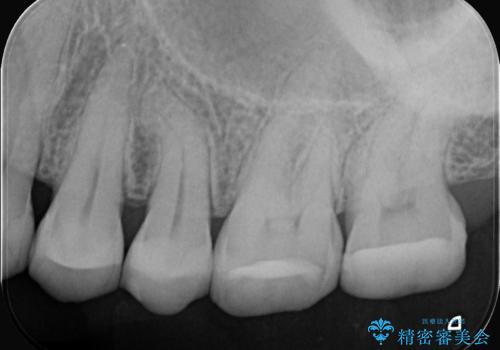

- 右上の歯の痛みを主訴にご来院されました。精密な診査の結果、虫歯が深く進行し、歯の神経(歯髄)にまで炎症が及んでいると診断。このままでは痛みが治まらず、歯を失うリスクもあるため、まず痛みの原因である感染した神経を取り除く根管治療を提案しました。根管治療によって歯の土台を整えた後、歯の破折を防ぎ長期的に機能させるため、**クラウン(被せ物)**を装着して修復する治療計画を立案しました。

治療はまず、感染源を徹底的に除去する根管治療から開始しました。治療の精度を高めるため、ラバーダムや顕微鏡などを使用し、根管内を丁寧に清掃・消毒。これにより、痛みの原因を根本から取り除きました。

根管治療が完了し、歯の内部が清潔で安定した状態になった後、歯を保護し、強い咬合力に耐えられるよう**クラウン(被せ物)**を装着しました。クラウンは、患者様の希望や咬み合わせの状態に応じて、機能性・審美性に優れた素材を選択し、精密に作製しました。

- 根管治療により痛みや腫れがひかない事や、術後に痛みや腫れが生じる事、治療によるファイル破折やパーフォレーションなどの偶発症、術後の歯根破折を生じる可能性もあります